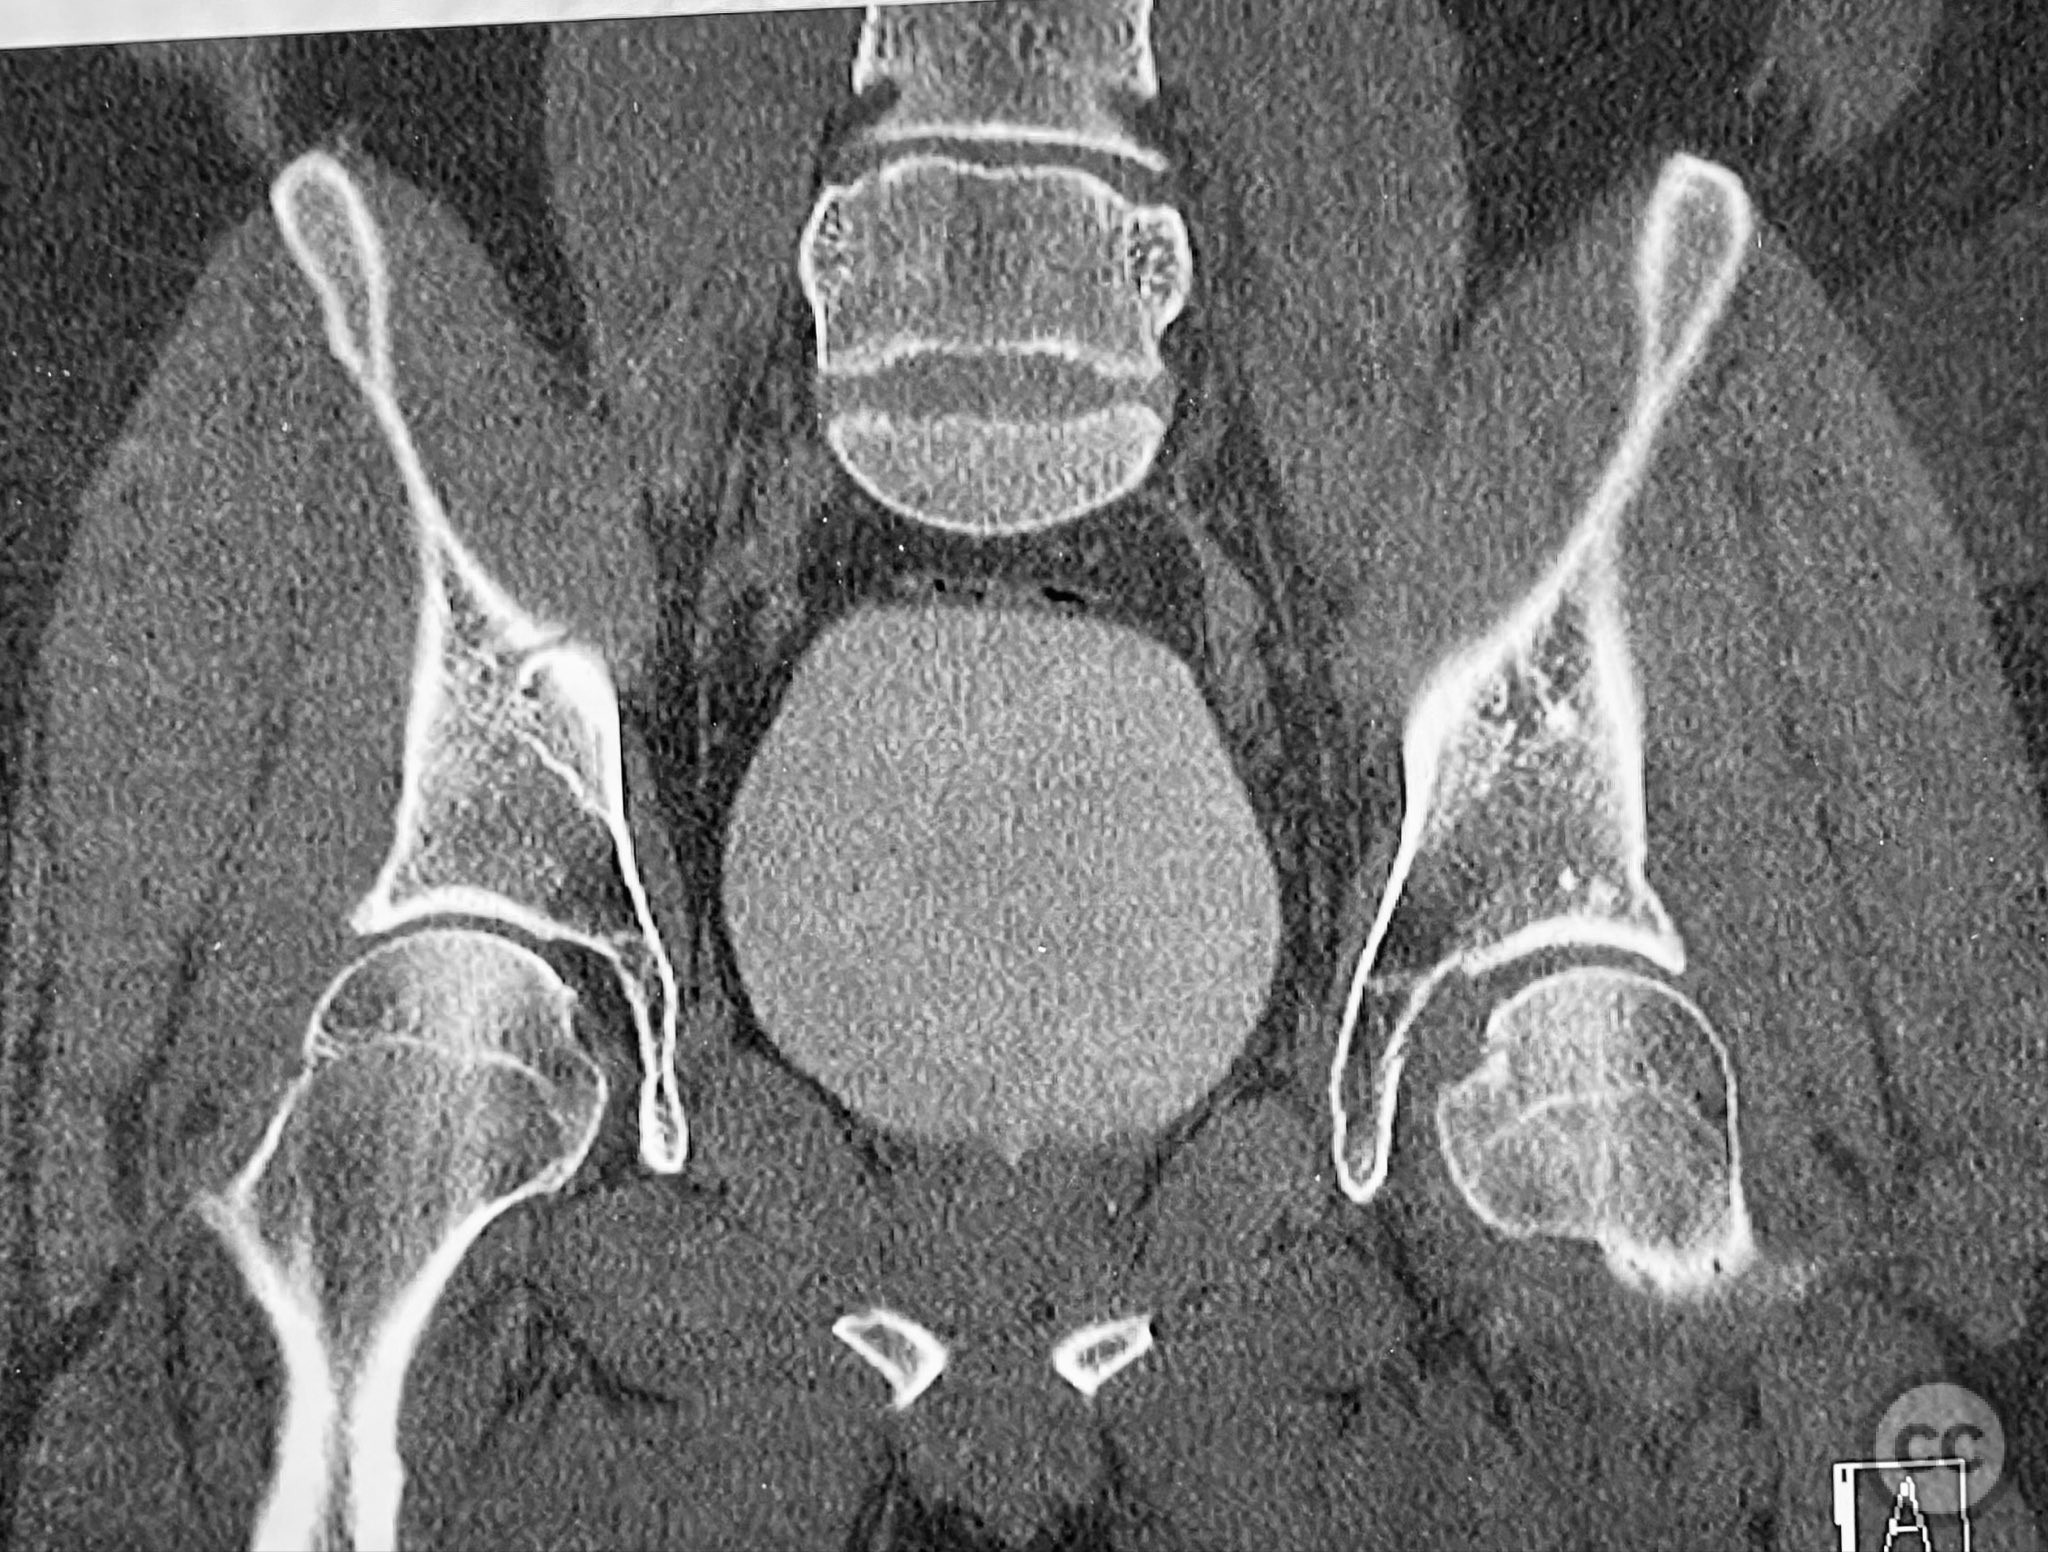

Clinical and radiological findings:  A patient involved in a motor vehicle collision presented with left hip pain exacerbated by any attempted movement. Initial axial and surface-rendered computed tomography (CT) imaging demonstrated an essentially nondisplaced posterior wall (PW) acetabular fracture (AO/OTA 62-A1.1). However, the anteroposterior (AP) scan image and coronal reconstructions revealed significant hip joint asymmetry. Examination under anesthesia with fluoroscopic guidance confirmed persistent joint incongruity, with the femoral head subluxating posteriorly at 50–60 degrees of flexion. A pure chondral fragment was identified as being interposed between the femoral head and the intact region of the posterior wall, accounting for the clinical and radiological asymmetry.